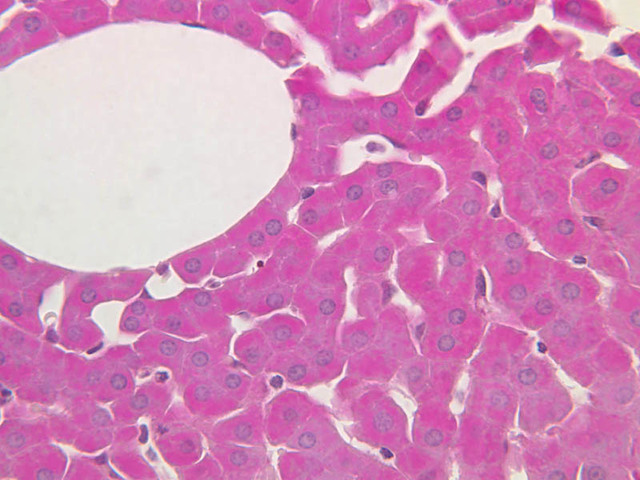

The structure of sinusoids can be studied in the liver (B-29, H&E [10x, 20x, 40x] [10x-labeled, 20x, 40x-labeled]; B-30, H&E [10x, 20x, 40x]; B-35, PAS [10x, 20x, 40x]) where they occur as endothelial tubes between plates of hepatocytes. In the liver, they are channels slightly larger in diameter than red blood cells and the individual lining cells have open spaces between them. The principal difference between sinusoids and capillaries is size, which presumably allows blood to flow more slowly in the larger sinusoids.

3 Sinusoids S H&E b29b sinusoids liver 40x labeled.jpgB29, Liver, 40x

4 Portal Vein PV H&E b29b sinusoids liver 40x labeled.jpgB29, Liver, 40x

5 Hepatic Artery HA H&E b29b sinusoids liver 40x labeled.jpgB29, Liver, 40x

6 Bile Duct BD H&E b29b sinusoids liver 40x labeled.jpgB29, Liver, 40x